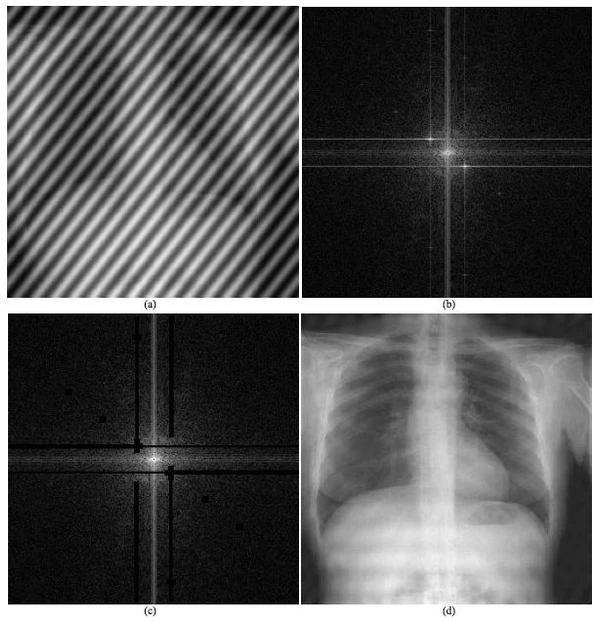

Важным применением информационной инженерии в медицине является обработка медицинских сигналов.[2] Это относится к генерации, анализу и использованию сигналов, которые могут принимать различные формы, такие как изображение, звук, электрические или биологические.[20]

Информатика медицинских изображений и компьютеризация медицинских изображений разрабатывают вычислительные и математические методы для решения проблем, связанных с медицинскими изображениями и их использованием для биомедицинских исследований и клинической помощи. Эти области направлены на извлечение клинически значимой информации или знаний из медицинских изображений и компьютерный анализ изображений. Методы могут быть сгруппированы в несколько широких категорий: сегментация изображений, регистрация изображений, физиологическое моделирование на основе изображений и другие.